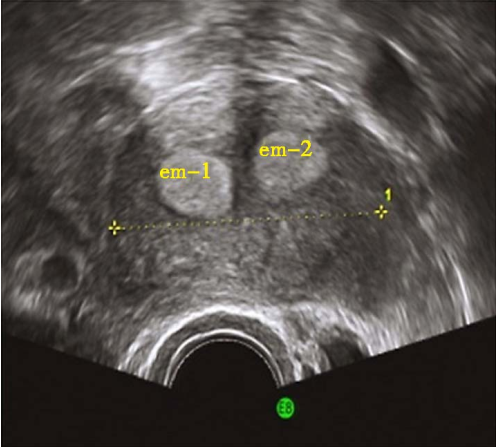

完全纵隔子宫二维超声

完全纵隔子宫三维超声

不完全纵隔子宫二维超声

一般无症状。临床上主要表现为影响生育期妇女的妊娠结局,包括反复流产、早产、胎膜早破等表现,其中以反复流产为最常见。经阴道超声检查是目前最常用的诊断方法,表现为两个内膜回声区域,子宫底部无明显凹陷切迹。子宫输卵管碘油造影(HSG)有助于了解宫腔形态,评估双侧输卵管通畅与否。宫腹腔镜联合检查是诊断纵隔子宫的“金标准”方法。